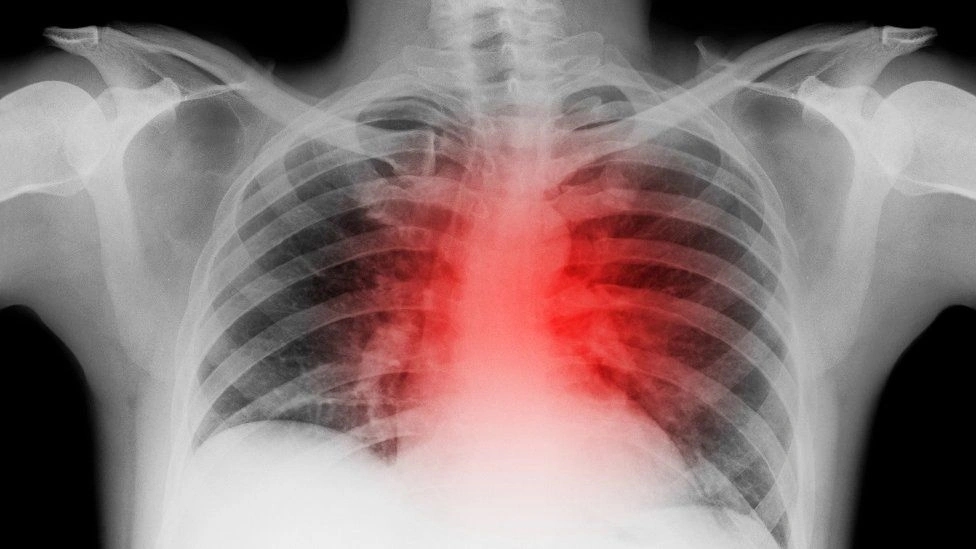

Nghiên cứu mới phát hiện ngay cả những người bị Covid-19 nhẹ cũng có nguy cơ đau tim, đột quỵ cao hơn. Ảnh: Shutter Stock.

Tim chỉ là một trong những cơ quan bị ảnh hưởng kéo dài vì Covid-19. Ảnh: BBC.